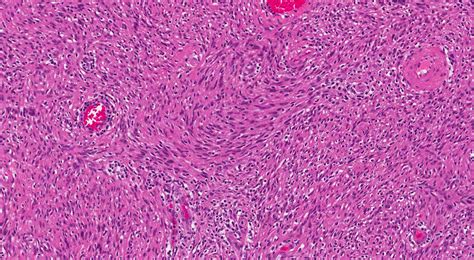

Spindle cell tumors are a diverse group of neoplasms characterized by spindle-shaped cells. These tumors can arise in various tissues and organs throughout the body, making their diagnosis and treatment a complex process. Understanding the different types, causes, symptoms, and treatment options for spindle cell tumors is crucial for both healthcare professionals and patients.

Spindle cell tumors are named for their distinctive spindle-shaped cells, which are elongated and tapered at both ends. These tumors can be benign or malignant, and their behavior can vary widely depending on the specific type and location. Some common types of spindle cell tumors include:

Each of these tumors has unique characteristics and requires different approaches to diagnosis and treatment.